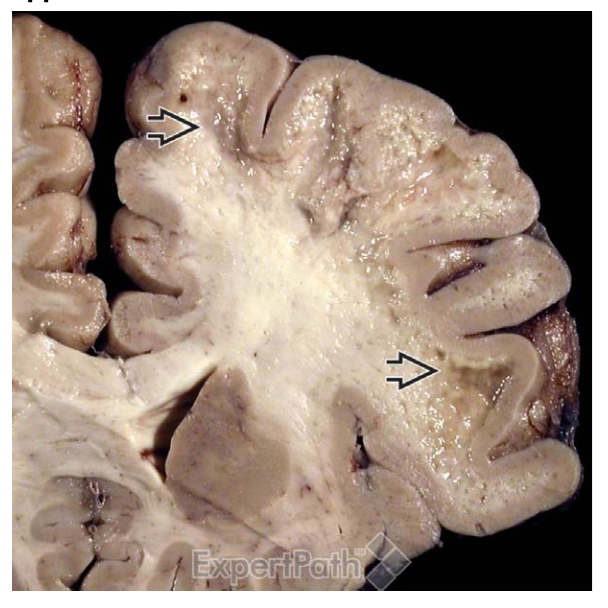

What patholgy is shown in the provided images? This is suspicious of what conditin?

If the provided sample has been stained with Luxol-fast blue PAS, it is from what disease?

sharp interface between lesion- demyelination - (left) and normal parenchyma (right)